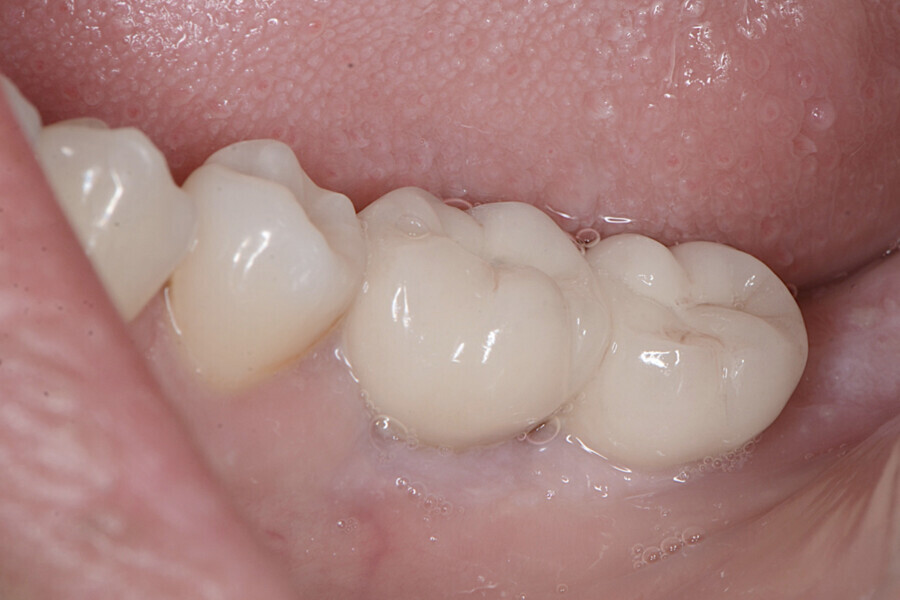

Aspect clinique de la zone des tissus mous péri-implantaires lors du suivi à cinq ans. (Photo : Dr Cosimir Dima)

Dix jours après l’intervention, les sites donneur et receveur étaient parfaitement cicatrisés (Figs. 15 et 16). Des visites de contrôle ont été prévues deux et quatre semaines plus tard, suivies de visites à trois, six et douze mois, puis tous les six mois pendant cinq ans (Figs. 17 à 20).

La profondeur de sondage du site péri-implantaire a été mesurée au niveau du point médian inter-proximal, et la valeur la plus élevée entre le bord des tissus mous et le fond du sulcus péri-implantaire a été retenue. Une lime endodontique ISO n° 15 a été utilisée pour évaluer l’épaisseur de la muqueuse péri-implantaire vestibulaire à 2 mm des bords des tissus mous en mésial, distal et médial de la plate-forme de l’implant (point de référence). La muqueuse kératinisée a été évaluée au début du traitement, puis lors des suivis au moyen d’une sonde parodontale. Les mesures ont été prises verticalement au niveau du point médio-vestibulaire, depuis la plate-forme de l’implant jusqu’au bord libre de la gencive. Elles ont été effectuées en préopératoire, immédiatement après l’intervention, puis à quatre semaines, un an et deux ans par la suite. Les paramètres cliniques (largeur de la muqueuse kératinisée, volume de la muqueuse, et recouvrement de la récession gingivale) ont été enregistrés au début du traitement, et lors de chaque visite de suivi. La largeur initiale de la muqueuse kératinisée était minimale (1 mm). À quatre semaines, le gain de largeur de la muqueuse kératinisée était de 2 mm, puis de 3 mm après un an, et de 4 mm après cinq ans.

À quatre semaines, le gain de volume de la muqueuse était de 3 mm, puis de 4 mm après un an, et de 5 mm après cinq ans. Le recouvrement de la récession était déjà complet après quatre semaines, et l’était toujours après un an et après cinq ans.